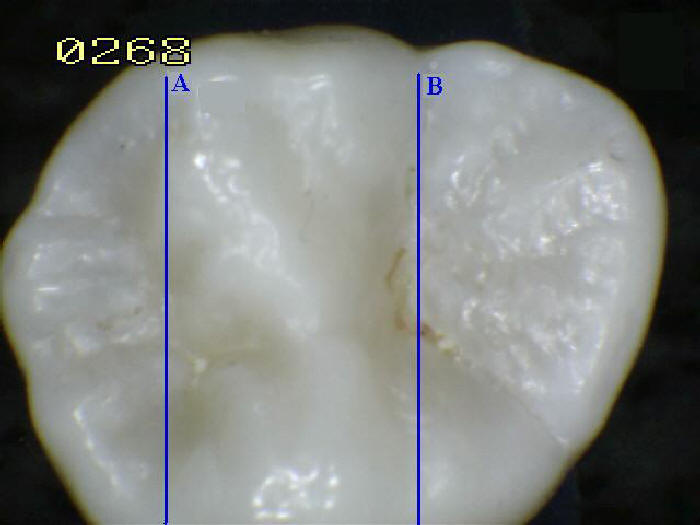

Ver imagen inferior.

VAINAS DE ESMALTE